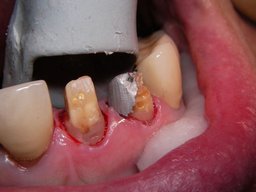

Weil auch die anderen Schneidezahnkronen (12-22) durch Randreparaturen und den schlechten Randschluß erneuerungsbedürftig aussahen, wurden 4 Einzelkronen geplant. Vorher hieß es aber noch, die schlechte Wurzelfüllung im Zahn 12 (Röntgenbild links) besser zu machen. Hierfür wurden am 17.2.06 die alten Kronen 11 und 12 entfernt. Rechts das Bild nach Entfernung von alten Füllungen und Karies.

Links nach Wurzelfüllung beim Einpassen des Titanstiftes. Rechts dann der schon provisorisch beschliffene Amalgamaufbau im Zahn 12.